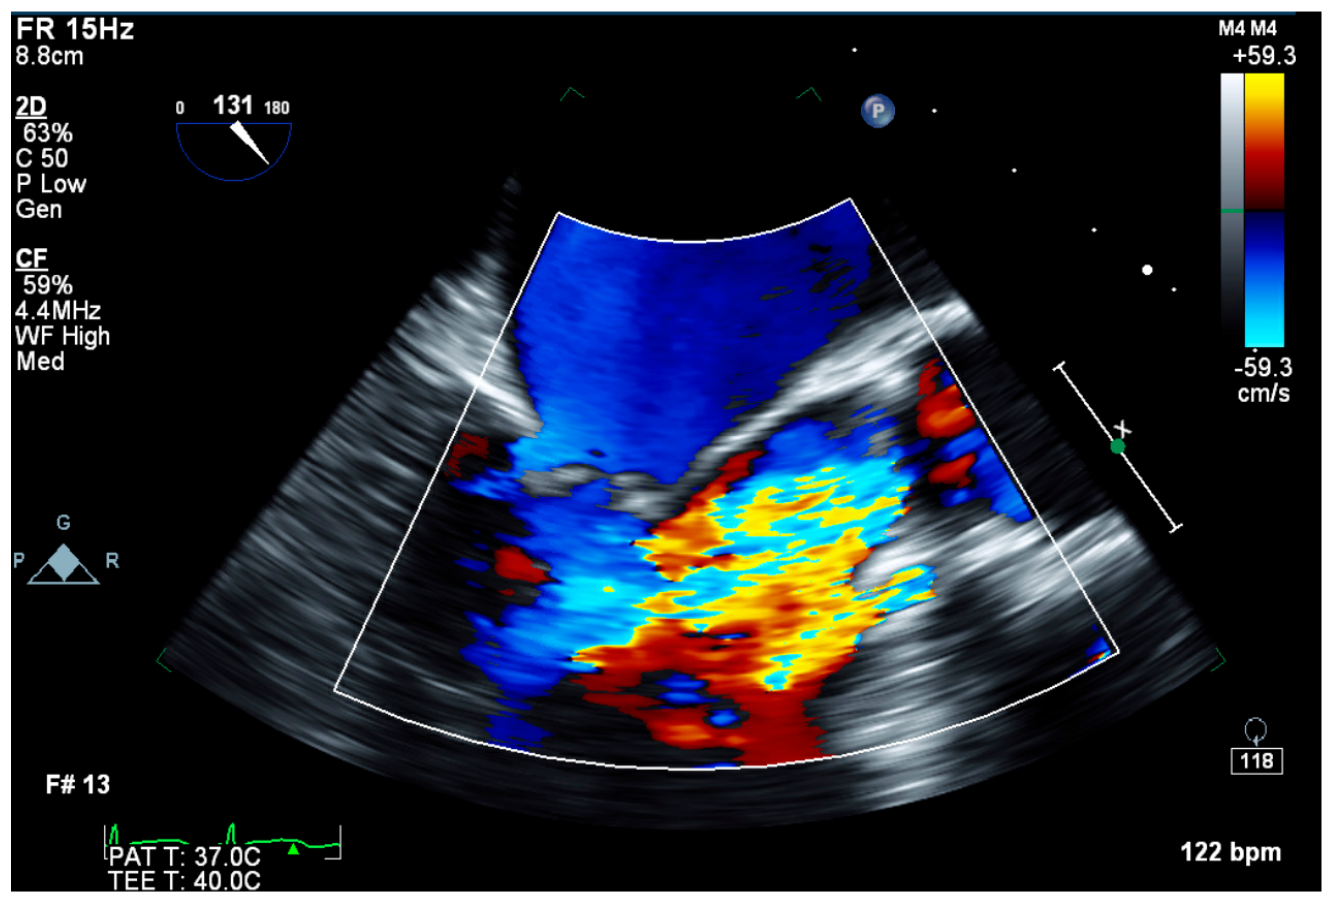

4. Investigations